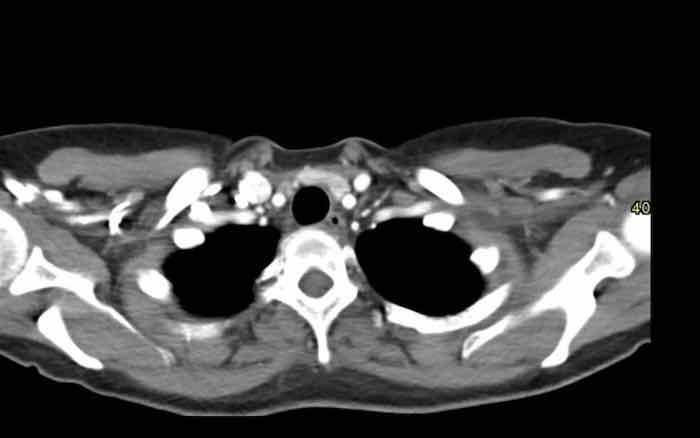

Các hình ảnh này của một phụ nữ 65 tuổi có tiền sử mắc bệnh Graves, một rối loạn tự miễn liên quan đến tình trạng cường chức năng tuyến giáp.

CT được thực hiện vì lý do ho ra máu.

Hình ảnh

Có một tuyến ức to lớn, cồng kềnh chứa mô mỡ đại thể.

Đây là hình ảnh điển hình của tăng sản tuyến ức.

Tăng sản tuyến ức trong bệnh Graves có liên quan đến tình trạng dư thừa hormone tuyến giáp và kháng thể kháng thụ thể thyrotropin.

Tình trạng này thường cải thiện sau khi điều trị thành công bệnh Graves.